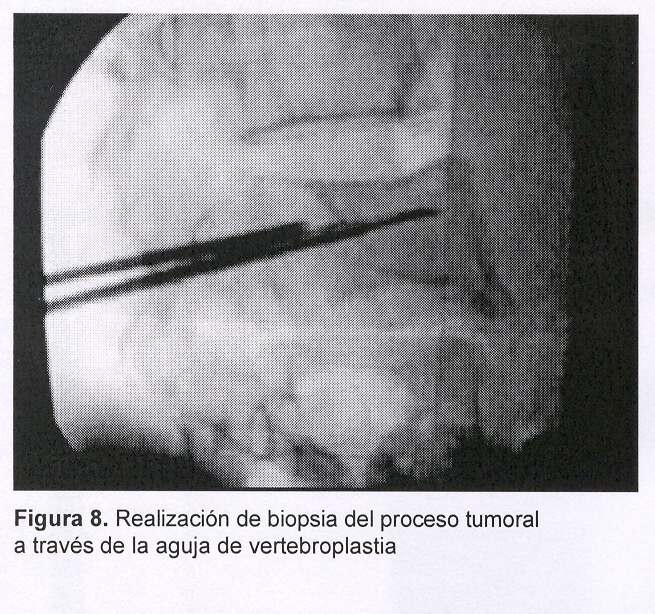

Sexo femenino, 43 años, con cuadro de 45 días de evolución dado por dolor raquídeo lumbar intenso, de comienzo súbito y evolución progresiva a pesar del tratamiento médico. Al igual que en el caso anterior el dolor era tan intenso que la obligaba a mantener reposo absoluto en cama. Al examen físico presentaba intenso dolor raquídeo a la palpación de L3, sin signología radicular ni deficitaria. Fue estudiada con radiografía simple (figura 5) y TC de columna lumbosacra que mostraban: aplastamiento del cuerpo vertebral de L3 a predominio de la plataforma inferior y falta de definición del pedículo derecho, múltiples imágenes líticas a nivel del cuerpo y del pedículo derecho con lisis parcial del muro posterior, abombamiento hacia el canal raquídeo (figura 6). Existían, además, otras imágenes líticas a nivel costal a la altura de la undécima costilla derecha. Las imágenes correspondían a sustitución ósea por metástasis. En esta paciente no existía noción de tumor primitivo por lo cual se planteó la realización de biopsia de la lesión concomitantemente con el tratamiento mediante vertebroplastia percutánea (figuras 7 y 8).